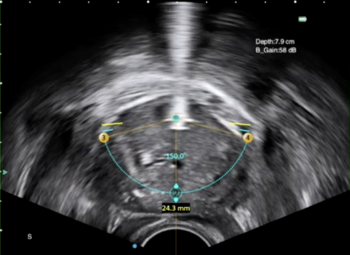

對於前列腺體積特別巨大的病人,一般較難把大部份前列腺組織有效地切除。在這種情況下,可以考慮其他的治療方案,例如前列腺水刀消融術和雙極/鈥激光前列腺剝離術。進行前列腺水刀消融手術的時候,我們會先在超聲波圖像上標記前列腺的輪廓,然後通過機械人控制的水射流技術進行消融。進行雙極/钬激光前列腺剝離術的時候,我們會先認清前列腺包膜的位置、然後把前列腺組織剝離及移除。

前列腺水刀消融手術